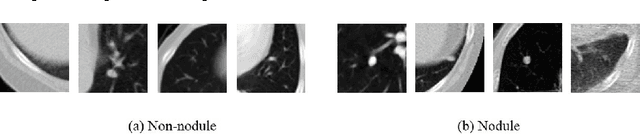

Lung nodule classification is a class imbalanced problem because nodules are found with much lower frequency than non-nodules. In the class imbalanced problem, conventional classifiers tend to be overwhelmed by the majority class and ignore the minority class. We therefore propose cascaded convolutional neural networks to cope with the class imbalanced problem. In the proposed approach, multi-stage convolutional neural networks that perform as single-sided classifiers filter out obvious non-nodules. Successively, a convolutional neural network trained with a balanced data set calculates nodule probabilities. The proposed method achieved the sensitivity of 92.4\% and 94.5% at 4 and 8 false positives per scan in Free Receiver Operating Characteristics (FROC) curve analysis, respectively.